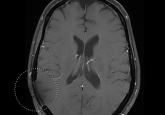

Multifocal Langerhans Cell Histiocytosis in an Adult

Eosinophilic granuloma (EG) is the most common and benign form of the spectrum of disorders referred to as Langerhans cell histiocytosis (LCH)....